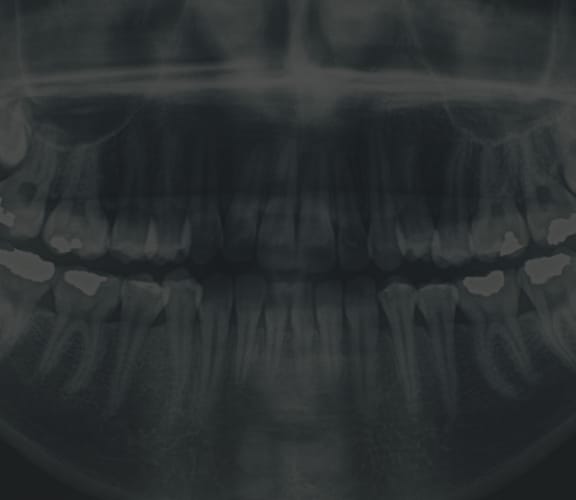

Crown lengthening is a surgical procedure that re-contours the gum tissue and often the underlying bone of a tooth. Crown lengthening is often for a tooth to be fitted with a crown. It provides necessary space between the supporting bone and crown, which prevents the new crown from damaging bone and gum tissue.

A gum lift may be performed to create a more even gum line. Patients with a gummy smile can quickly and safely have unwanted tissue removed, thus exposing more tooth to shape a more attractive smile.